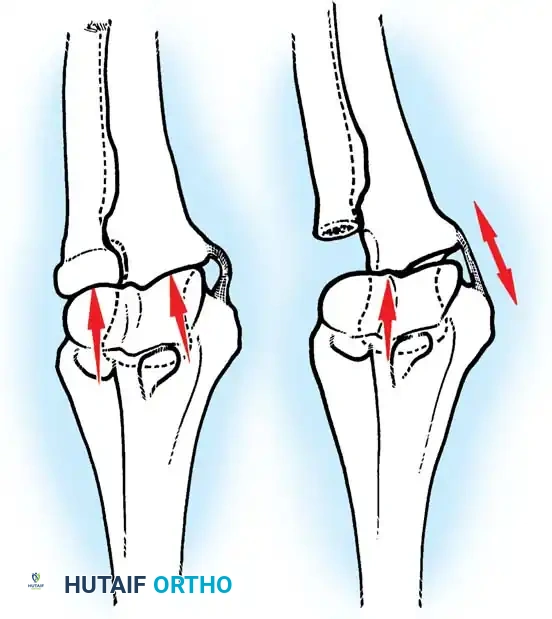

Joint reaction forces at the elbow are surprisingly high. Static analyses reveal that forces are greatest in extension and pronation. During strenuous lifting, compressive forces across the joint can reach three times body weight.

With the elbow extended and axially loaded, 40% of the stress is transmitted through the ulnohumeral joint, and 60% through the radiocapitellar joint. If the radial head is excised, the humeroradial force is entirely shifted to the ulna. This drastically increases tension on the MCL and concentrates massive loads on the lateral edge of the coronoid process, potentially applying forces up to nine times body weight to the medial structures.